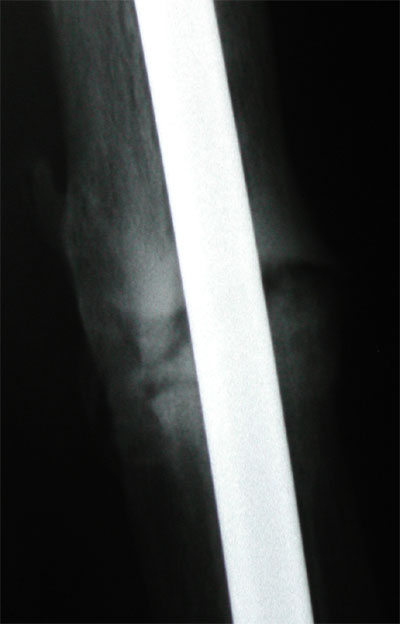

August 30, 2005 X-ray update

Heck, even I am starting to think the backside is really healing. The later x-ray, on the right, is a little darker, but shows some organized remodeling along what represents the back of the leg. The doctor argues that healing starts there and works it way around to the front. I will have a front x-ray next time. In the meantime he takes it as good signs that I am feeling a little better, certainly not worse, and that the x-ray looks better and not worse. Such optimism. I also think I am reabsorbing some of that stray bone in the muscle as well.